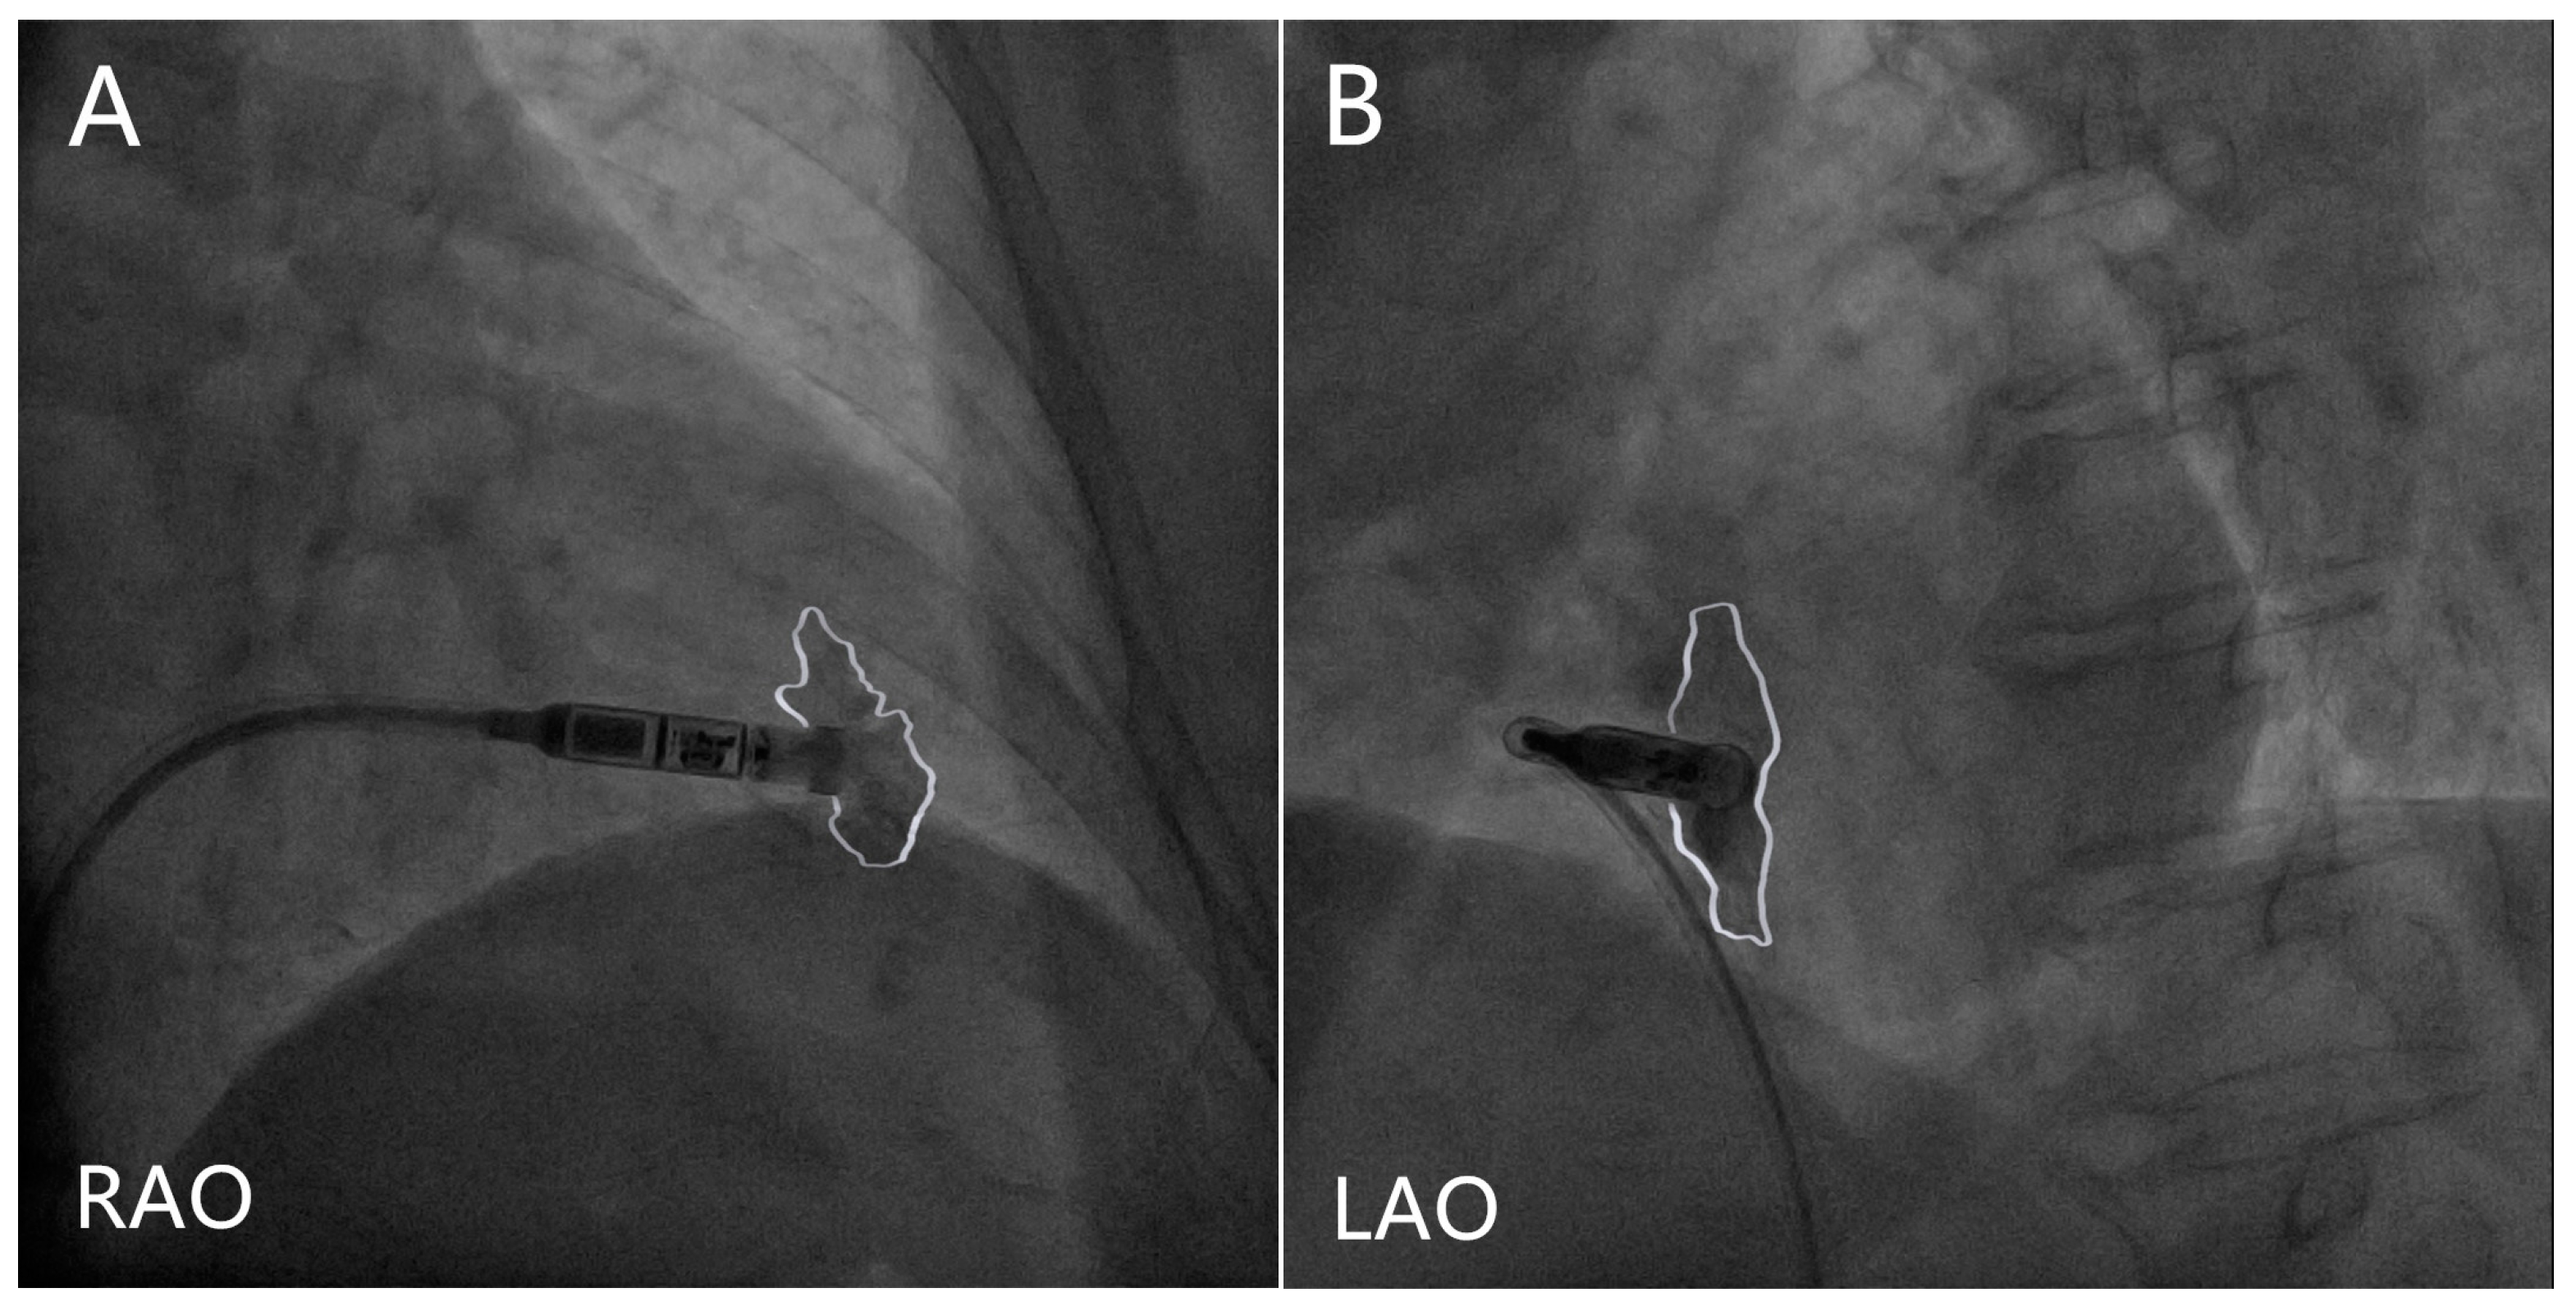

- Device programming: The nominal values of the Micra AV were optimized for patients during resting. Regular postimplant device reprogramming is necessary and should be individually optimized. The manual atrial mechanical (MAM) test is to line up A1–A4 signals with the corresponding surface ECG signals (Figure 2). Firstly, the MAM test with “auto” atrial mechanical features turned-off runs in the VDI mode to allow a clear distinction of the A1–A4 signals, and subsequently, MAM test runs in the VDD mode to make adjustment based on the track of atrial activity. The systematic and stepwise approaches including MAM test and adjustments of the A4 threshold, A3 window, and A3 threshold are to accurately discern A4 [78,79].

- The A4 threshold: In situations of low A4 amplitudes, a lower A4 threshold facilitates a reduction in the under-sensed A4 and improves the AV synchrony [72,73]; Meanwhile, in the case of low A4 amplitudes, the device’s built-in 3-axis accelerometer atrial-sensing vectors can be changed from a selection of one or two vectors to a recruitment of all three vectors to improve AV synchrony at the cost of negative impact on battery longevity [78,79]. When the A4 threshold is too low, the over-sensed A4 could impair the AV synchrony, which was observed in a study in which a higher A4 threshold was found to be related to a higher AV synchrony [74] (Figure 3A);

- The A3 window end: In situations of sinus tachycardia, the A4 signal falls in the A3 window, which reduces the AV synchrony. A shorter A3 window end interval for detecting the A4 signal and improving the AV synchrony has been confirmed in multiple studies [72,73,74]. A rate-dependent A3 window may be promising for tracking atrial contractions at higher heart rates. However, some researchers have suggested setting the A3 window below 700 ms and deactivating the automatic adjustment to improve the AV synchrony [74] (Figure 3B);

- The A3 threshold: In situations of sinus tachycardia, the A4 signal begins with the encroachment into the A3 window; however, as the heart rate is further elevated, the A4 signal could merge with the A3 signal and the A3 auto threshold function could result in the under-sensing of A4. Turning the A3 auto threshold function off and fixing the A3 threshold contribute to AV synchrony, and this is especially suitable for elevated sinus rates of 80–110/min [71]. A lower A3 threshold could improve the AV synchrony [74,76] (Figure 3C);

- The PVAB: In situations of Wenckebach behavior, the progressive shortening of the RP interval means that the P wave falls in the PVAB period, which results in the intermittent loss of A4 [76]. Shortening the PVAB to minimize the p-wave blanking is recommended. Wenckebach behavior occurs in patients with intrinsic conduction for whom the AV synchrony is high; therefore, the benefit of shortening PVAB is limited (Figure 3D);